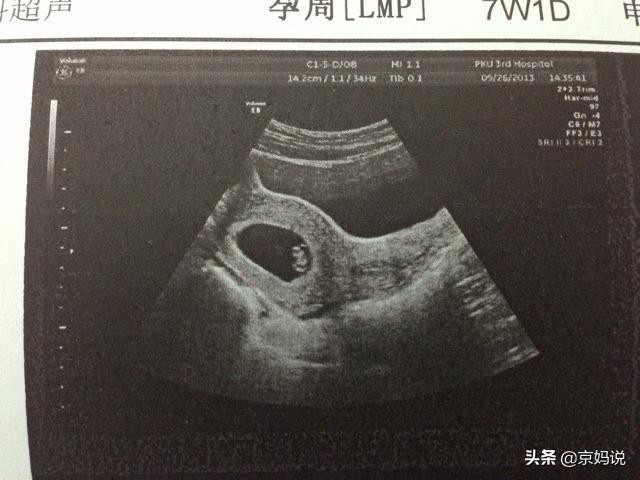

怀孕胎停和体温下降的关系